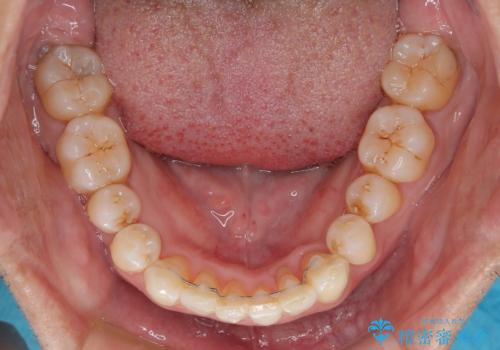

担当医としてはもう少し前歯のデコボコを改善したいところでしたが、患者様としては十分に満足いく歯列であり、マウスピース矯正に飽きてしまったとのことで、治療終了となりました。